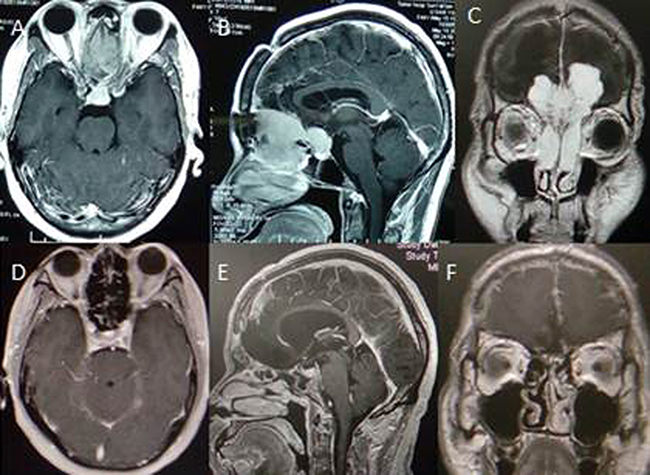

We reviewed computed tomography (CT) and MR images to identify patients with tumours meeting our definition of OGM with extracranial invasion like (Figure 3A–3C). Tumours ranged from 4.0 to 8.0 cm in diameter (mean, 5.5 cm). The tumours eroded the mucous membrane of the sinuses and extended into the sinal cavity. Age, gender, size, oedema, T2 signal, bone hyperostosis and destruction were analysed in statistics. No adjuvant therapy was administered, with the exception of radiotherapy in two patients. Tumour histological diagnosis coincided with the WHO I criteria, with the exception of one atypical case. The classification of tumour pathology was diversified. All patients received follow-up with clinical examination and MRI studies three months and one year after surgery like Figure 3D–3F. Thereafter, patients were re-examined regularly at one-or two-year intervals based on each follow-up result. The duration of follow-up ranged from 66 to 159 months (median, 91.8 months).

Figure 3: Cranial MR image displaying olfactory groove tumor with nasal cavity extension and follow-up with no recurrence.